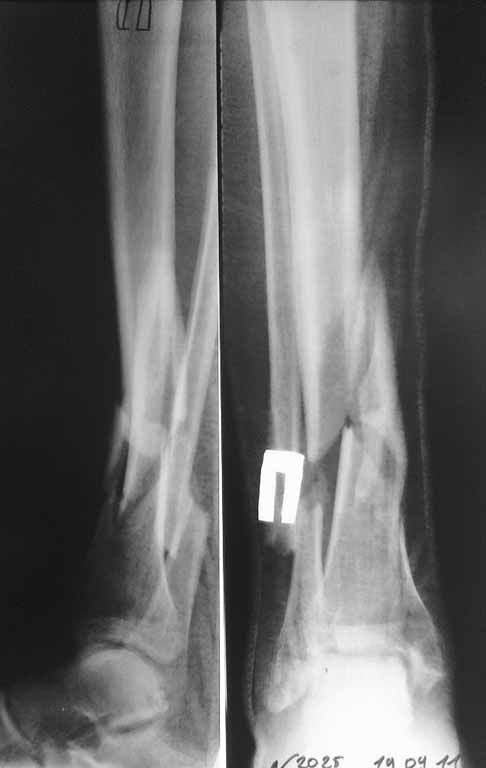

спасибо за участие. Перелом голени выложил сегодня из-за проблем с интернетом. На этой неделе запланирована попытка синтеза бедра, длинный PFN ChM, на ортопедическом столе, все-таки планирую открывать зону перелома сразу. Голень на следующей неделе.

Уважаемый Сергей! Следует уточнить(для уважаемого сообщества) , что переломы находятся на разных конечностях, поэтому восстановление длины бедра потребует равнозначной коррекции длины голени. Либо, как предлагает профессор Djoldas Kuldjanov, не добиваться полной репозиции и пожертвовать частью дистального отломка, сохранив ось и ротацию. Корригировать длину голени проще ввиду меньших усилий по преодолению ретракции мягких тканей. Хотя пациент молодой и желательно наиболее полно восстановить конечности. Несомненно,аппарат Илизарова собирать долго и нудно и неохота, но возможность управляемой фиксации при минимальных экономических затратах перевешивает данные "недостатки". Да и не располагаем АО фиксаторами, гексаподами. Следует учесть и то , что при одномоментной коррекции длины голени (3,5 - 4 см) могут возникнуть трудности с зашиванием и заживлением операционных доступов. Еще позволю уточнить, что клинических признаков консолидации на голени нет - подвижность полная, что не потребует остеотомии малоберцовой кости. Поэтому желаю Вам, Сергей, удачи в одномоментной коррекции деформации бедра и остеосинтезе, но нужно быть готовым к варианту Александра Николаевича - дистрактор, дозированная коррекция смещения по длине, остеосинтез.

K сожалению, Вы не указали на сторону перелома голени. Если со стороны перелома бедра, то это ухудшит ситуатцию для дистракции... Также нет снимков голени